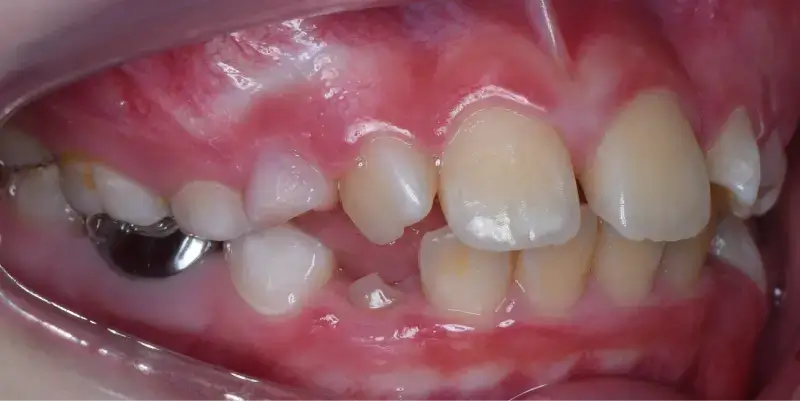

兒童早期矯正,又稱為「預防性矯正」或「第一階段矯正」,指的是在孩子乳牙或混合牙期(約7~10歲)時,就針對牙齒排列、咬合不正、牙弓發育等問題提前介入的矯正治療。 目的不只是「把牙齒排整齊」,更重要的是引導上下顎正常發育,減少未來拔牙、正顎手術的機率,讓恆牙有足夠空間健康萌發。

透過早期擴大牙弓、改善空間,能降低日後因擁擠而必須拔牙的情況。

相當於國小低至中年級,這時會開始進到乳牙換成恆牙的階段,也是牙齒移動速度快的時期,在這個階段接受矯正能夠擁有良好的矯正效率,因此也被定義為「兒童矯正的黃金期」。

早期矯正屬於「第一階段」,目的是為了改善結構性問題與預防性治療,等恆牙長齊後,或許可能需要第二階段矯正做細部微調,但相較從未矯正過的孩子,已做早期矯正的小朋友通常不需拔牙、減少正顎手術的風險,而且療程也會更短。